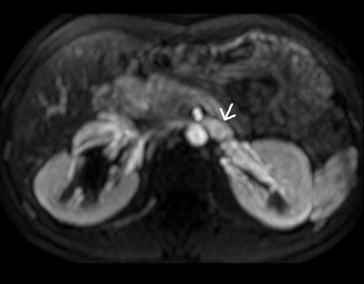

Renal Doppler ultrasound was performed, and peak velocity (PV) was measured at the hilar and aortomesenteric portions of the LRV. In the upright position, the PV in the hilar and aortomesenteric portion of the LRV were 28.4 and 200 cm/s, respectively, and the PV ratio was 7.04; the anteroposterior diameters were 11.1 mm and 1.3 mm (Fig. 1), respectively, and the ratio of the AP diameters was 8.6. The pressure gradient between LRV and inferior vena cava was 16 mmHg. It also showed dilatation of the right renal pelvis. Magnetic resonance angiography (MRA) showed that the LRV is compressed between the AO and the SMA, and the hilar portion of the LRV was distended (Fig. 2). The SMA delineated sharply from the AO, and the aortomesenteric angle where the LRV crosses was 15°. Retrograde pyelograthy (Fig. 3) and magnetic resonance urography revealed right-sided ureteropelvic junction stenosis and hydronephrosis. From these findings, a diagnosis of left nutcracker syndrome and right UPJO was made.

Doppler ultrasound showing nutcracker phenomenon. Narrowing aortomesenteric ...

Doppler ultrasound showing nutcracker phenomenon. Narrowing aortomesenteric portion (arrow) of the left renal vein.